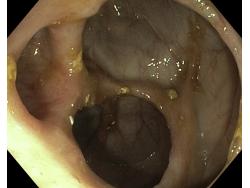

Choroba Leśniowskiego-Crohna